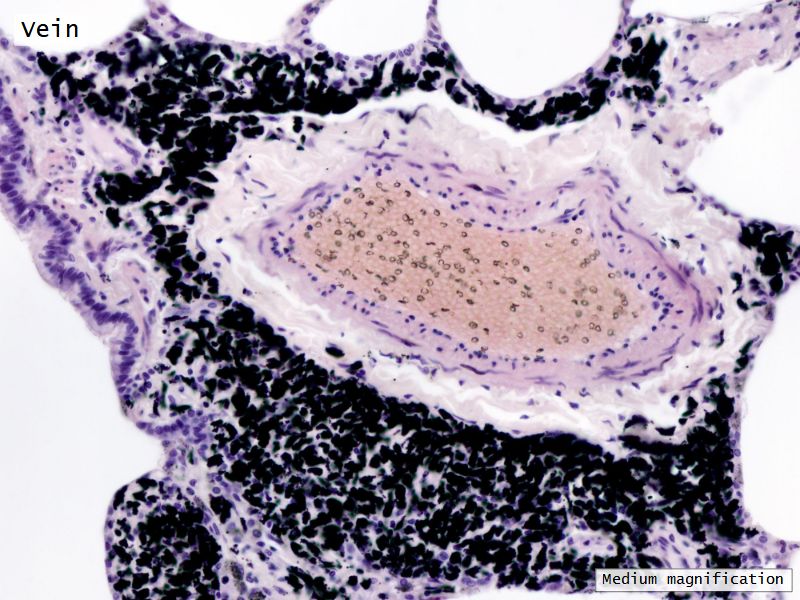

Respiratory epithelium